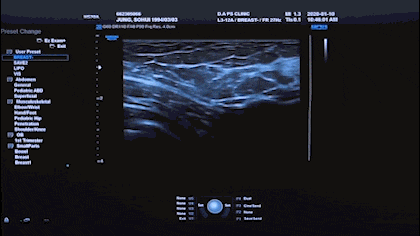

The thickness of capsule can only be identified and Measured through very high-resolution ultrasound due to its' thickness is below 1mm which is very thin.

Thickness of normal capsule forms within 0.1 to 0.3 mm, however Thickness of abnormal capsule due to capsular contracture forms

over 0.6mm. If the top of capsule seems thick, then

Breast Ultrasound By A Breast Specialist

It is available to take a breast ultrasound which is

specialized in breast Disease